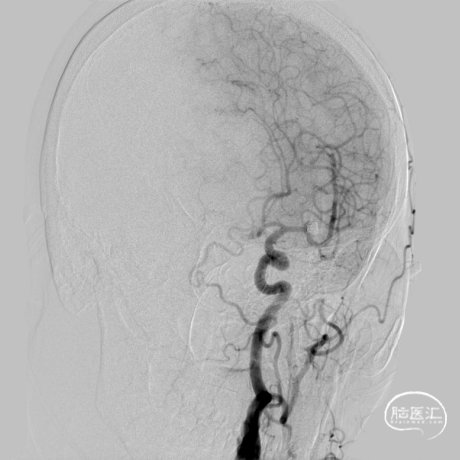

术前造影

患者推入放射科导管室平躺于检查床上,常规心电、血压监护;消毒右侧腹股沟区,铺手术巾,气管插管全身麻醉后,穿刺右侧股动脉,置入导管鞘,成功后置入超滑导丝及椎动脉导管,行左侧颈内动脉3D造影术,明确动脉瘤栓塞和辅助支架置入的工作体位。

载瘤动脉细小,经测量为0.87mm,角度为反向角度,释放支架易贴壁不良,颈内动脉段血管入路较迂曲,需要支撑力及柔顺性较好的微导管,同时避免微导管拉直血管并使血管位移而影响定位。